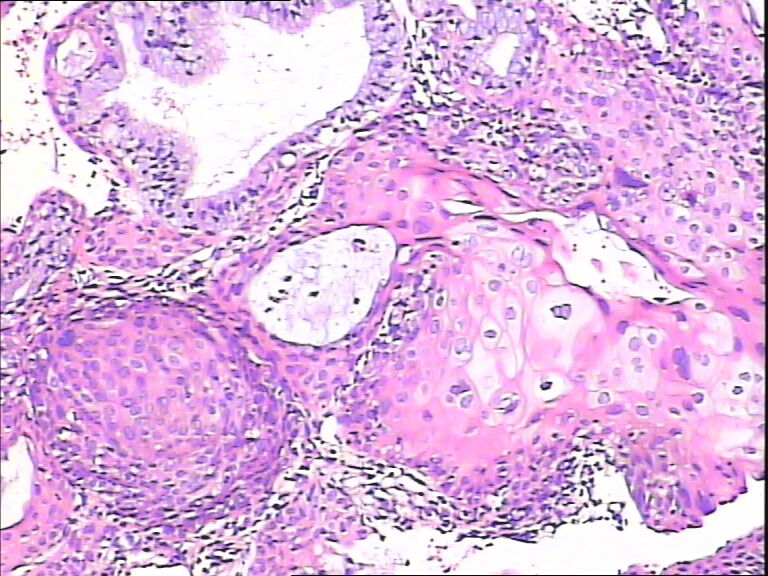

45y,触血,宫颈多点活检。